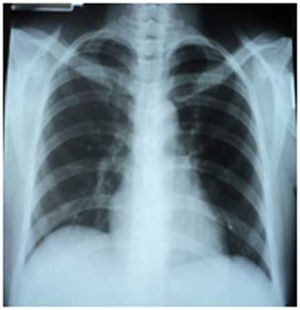

Case history: Patient first reported to the hospital on May 15, 2013, with complaint of severe right shoulder pain and at some times breathlessness.